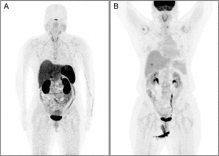

为了尽快控制病情,张阿姨接受了完全切除术,然而不幸的是,手术后不久就出现了转移,并且由于她的生长抑素受体表达极低,生长抑素类似物和肽受体放射性核素治疗等常规手段均无法应用,只能不断尝试各类化疗药物。让医生束手无策的是,在使用了包括卡铂、依托泊苷、卡培他滨、替莫唑胺、紫杉醇在内的多种化疗药物,以及依维莫司和阿特珠单抗等治疗方案后,肿瘤仍在疯狂增长,张阿姨病情持续恶化,出现无数皮下结节、左侧胸膜转移、多发性骨转移和脑转移等严重状况...

就在治疗陷入绝境时,医生决定做最后的尝试,为张阿姨进行全基因检测,结果惊喜的发现,张阿姨的基因出现了一种非常罕见的突变类型: ETV6-NTRK2 融合基因。针对这一靶点已上市的拉罗替尼和恩曲替尼数据都非常鼓舞人心,很多患者接受治疗后重返正常生活。

基于这一发现,医疗团队迅速调整策略,为张阿姨启用第一代原肌球蛋白受体激酶抑制剂恩曲替尼(600 毫克,每日一次)进行治疗。

奇迹就这样发生了,治疗仅1个月迅速起效,张阿姨所有转移性肺病灶实现完全缓解。更令人欣喜的是,从开始接受恩曲替尼治疗至今,已持续获益至少一年,目前治疗仍在顺利进行中。